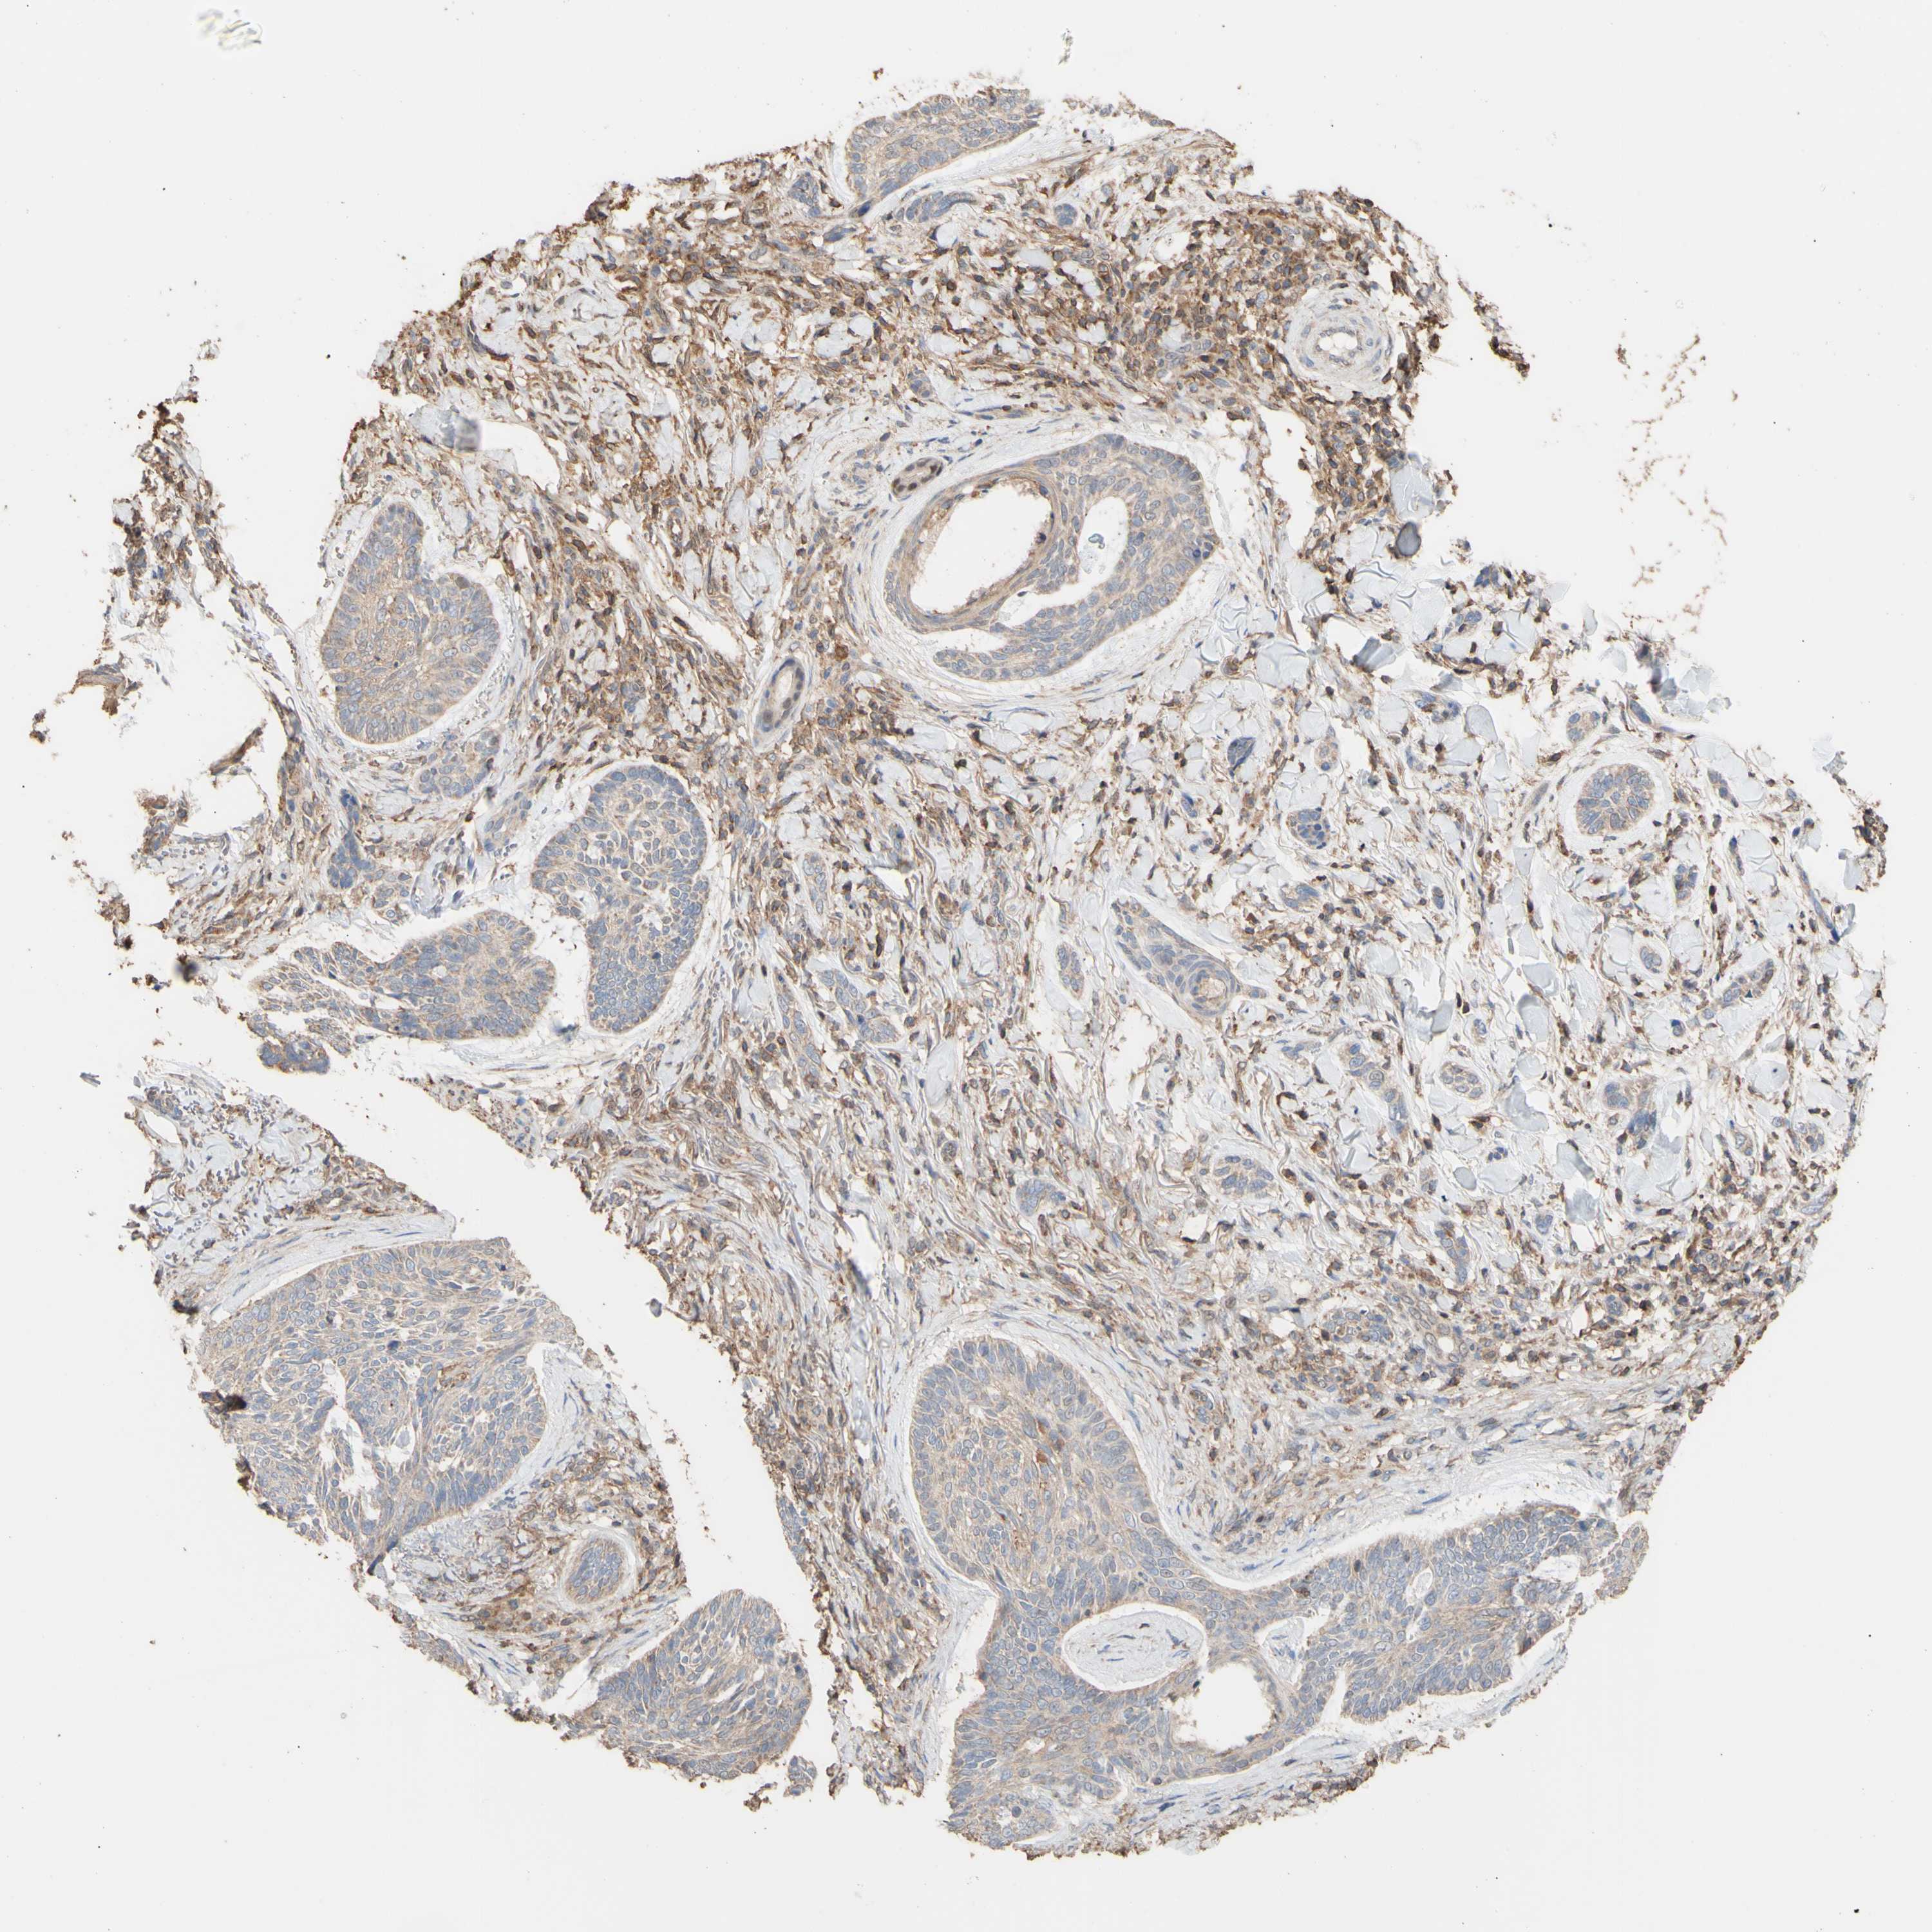

SKIN CANCER - Protein expressioni

A mouse-over function shows sample information and annotation data. Click on an image to view it in a full screen mode. Samples can be filtered based on level of antibody staining by selecting one or several of the following categories: high, medium, low and not detected. The assay and annotation is described here.

Antibody staining in the annotated cell types in the current human tissue is reported as not detected, low, medium, or high, based on conventional immunohistochemistry profiling in selected tissues. This score is based on the combination of the staining intensity and fraction of stained cells.

Each image is clickable and will lead to virtual microscopy that enables deeper exploration of all samples and also displays staining intensity scores, fraction scores and subcellular localization as well as patient and tissue information for each sample.

Antibody HPA010873

Staining

High

Medium

Low

Not detected

Intensity

Strong

Moderate

Weak

Negative

Quantity

>75%

75%-25%

<25%

None

Location

Nuclear

Cytoplasmic/membranous

Cytoplasmic/membranous,nuclear

Squamous cell carcinoma, NOS

Basal cell carcinoma

Adnexal tumor, benign